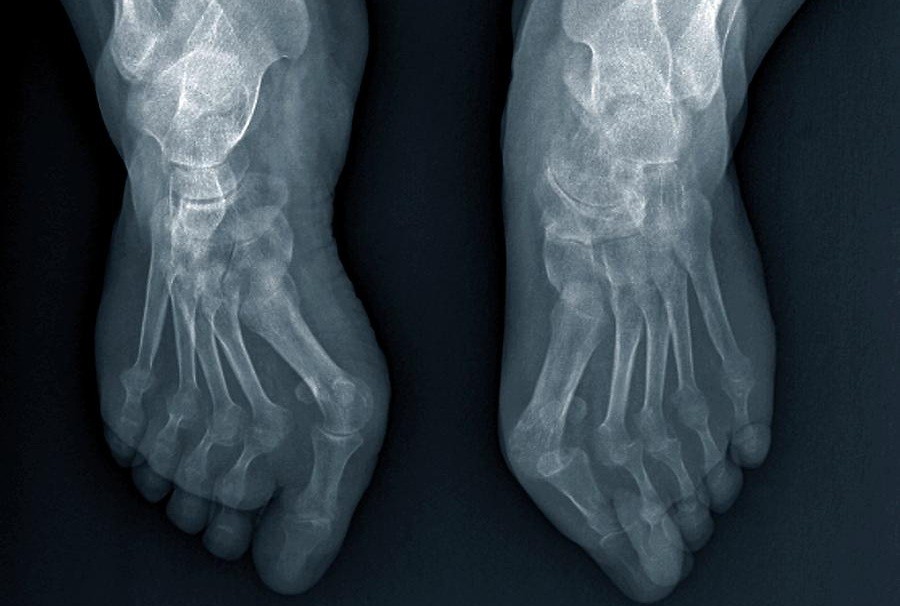

Jari tangan bengkok akibat keausan akibat usia dan artritis lanjut.

Pria, 69 tahun. Osteoartritis pada jari kaki, kelengkungan dan deformasi yang parah. "Jointlite" sepenuhnya memulihkan sendi dan mengembalikan jari ke posisi normal dalam 2,5 bulan.